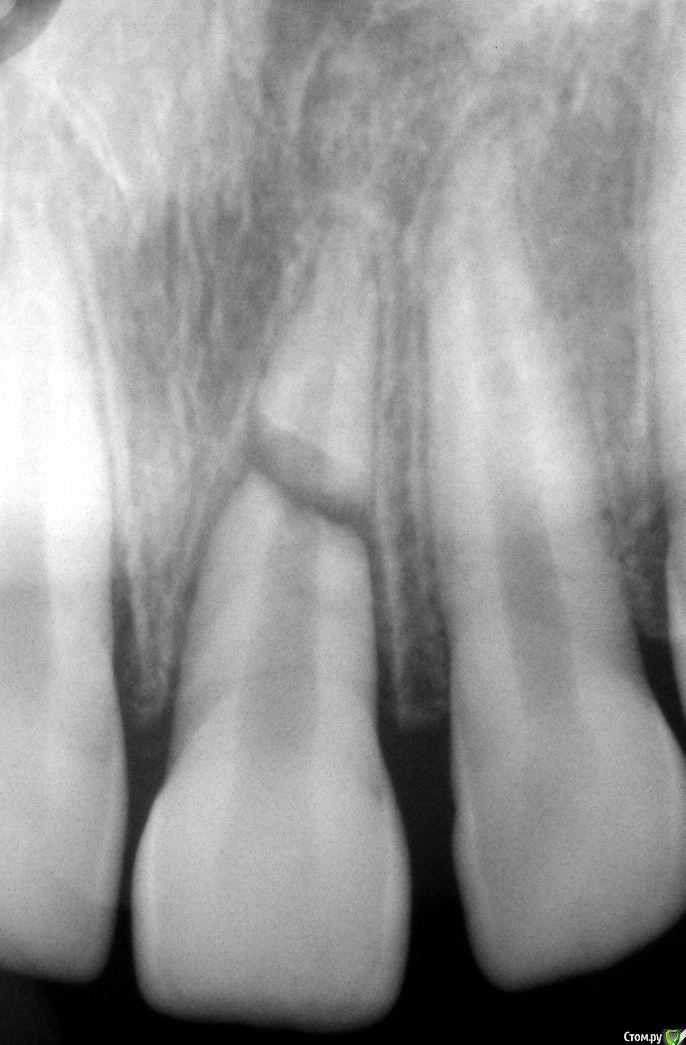

Давлетшин Опубликовано 15 декабря, 2016 Поделиться Опубликовано 15 декабря, 2016 (изменено) Пациент пришел после ЧЛО. Катался на велосипеде. 11 лет. Простите как давно была травма? до прихода к вам. Просто катался на велосипеде 13 декабря? Пришел после ЧЛО. он там долго находился?Если летом была травма а попал к вам сейчас то прогноз очень неблагоприятный. от слова совсем.Если сутки двое при данных объективных условиях и данной R-грамме, я в первую очередь старался бы купировать воспаление. Как? не претендую на первую инстанцию.1) правильное эндо обоих2) в канале оставил бы Пульпосептин (Греназоль)3) под слизистую линкомицин 30%-1,0+лидокаин 2%-1,0 №5 каждый день №1 (тут может быть дисскуссия об антинаучном подходе, но я так делал и результаты радовали)4) шинирование, само собой, НО не забыть о репозиции отломков, исключении из прикуса ( в нашем случае уменьшение периодонтальной щели)5) при благоприятном исходе, через 2-3 мес, пломбирование канала, удаление верхушки коря, по типу резекции. как мне думается в данном клиническом случае общая тактика лечения заболевания должна исходить не как от травмы, а как от острого травматического периодонтита.( можно и по другому обозвать, суть что после ортодонтов такое есть)у меня выработался момент шинирования в том, что после репозиции в качестве шин лигатур я исползовую композит жидкотекучий в межзубные промежутки, также не надо стесняться мобилизацию переделывать, на повторной R-графии, после шинирования. Изменено 15 декабря, 2016 пользователем Давлетшин Ссылка на комментарий

vse32 Опубликовано 15 декабря, 2016 Поделиться Опубликовано 15 декабря, 2016 ТАК все таки сусудисто-нервный пучок восстанавливается? Может ТАК корень может сраститься? сраститься с чем между отломками корня иль с альвеолярным отростком? Может. Срастаются обломки с образованием костной мозоли. Еще добавлю от себя.Обязательное назначение антибиотиков сразу после травмы. В случае установления некроза сосудисто-нервного пучка - эндо только коронарного отломка. Апикальный не трогается вовсе. Не извлекается, не эндодотируется. Ничего. 1 Ссылка на комментарий

Давлетшин Опубликовано 3 февраля, 2017 Поделиться Опубликовано 3 февраля, 2017 (изменено) Значит и здесь не повезло. Удар никуда не обращался. Через 5-7 лет разболелось, Начали делать эндо, что то не то. На КТ , потом к хирургу.Думается ошибка пациента была, что не зашинировал, сразу. Изменено 3 февраля, 2017 пользователем Давлетшин Ссылка на комментарий

vse32 Опубликовано 3 февраля, 2017 Поделиться Опубликовано 3 февраля, 2017 Это же внутренняя теперь уже перфорирующая резорбция. Никак себя не проявляет. Только при присоединениии вторичной инфекции появляются симптомы. Шинирование или ещё чего от неё не спасёт. На ранних стадиях выявляется случайно. Ошибка пациента, что не обратился грамотному врачу, который бы назначил динамическое наблюдение и вылечил зуб на начальной стадии. Теперь только удаление. Ссылка на комментарий